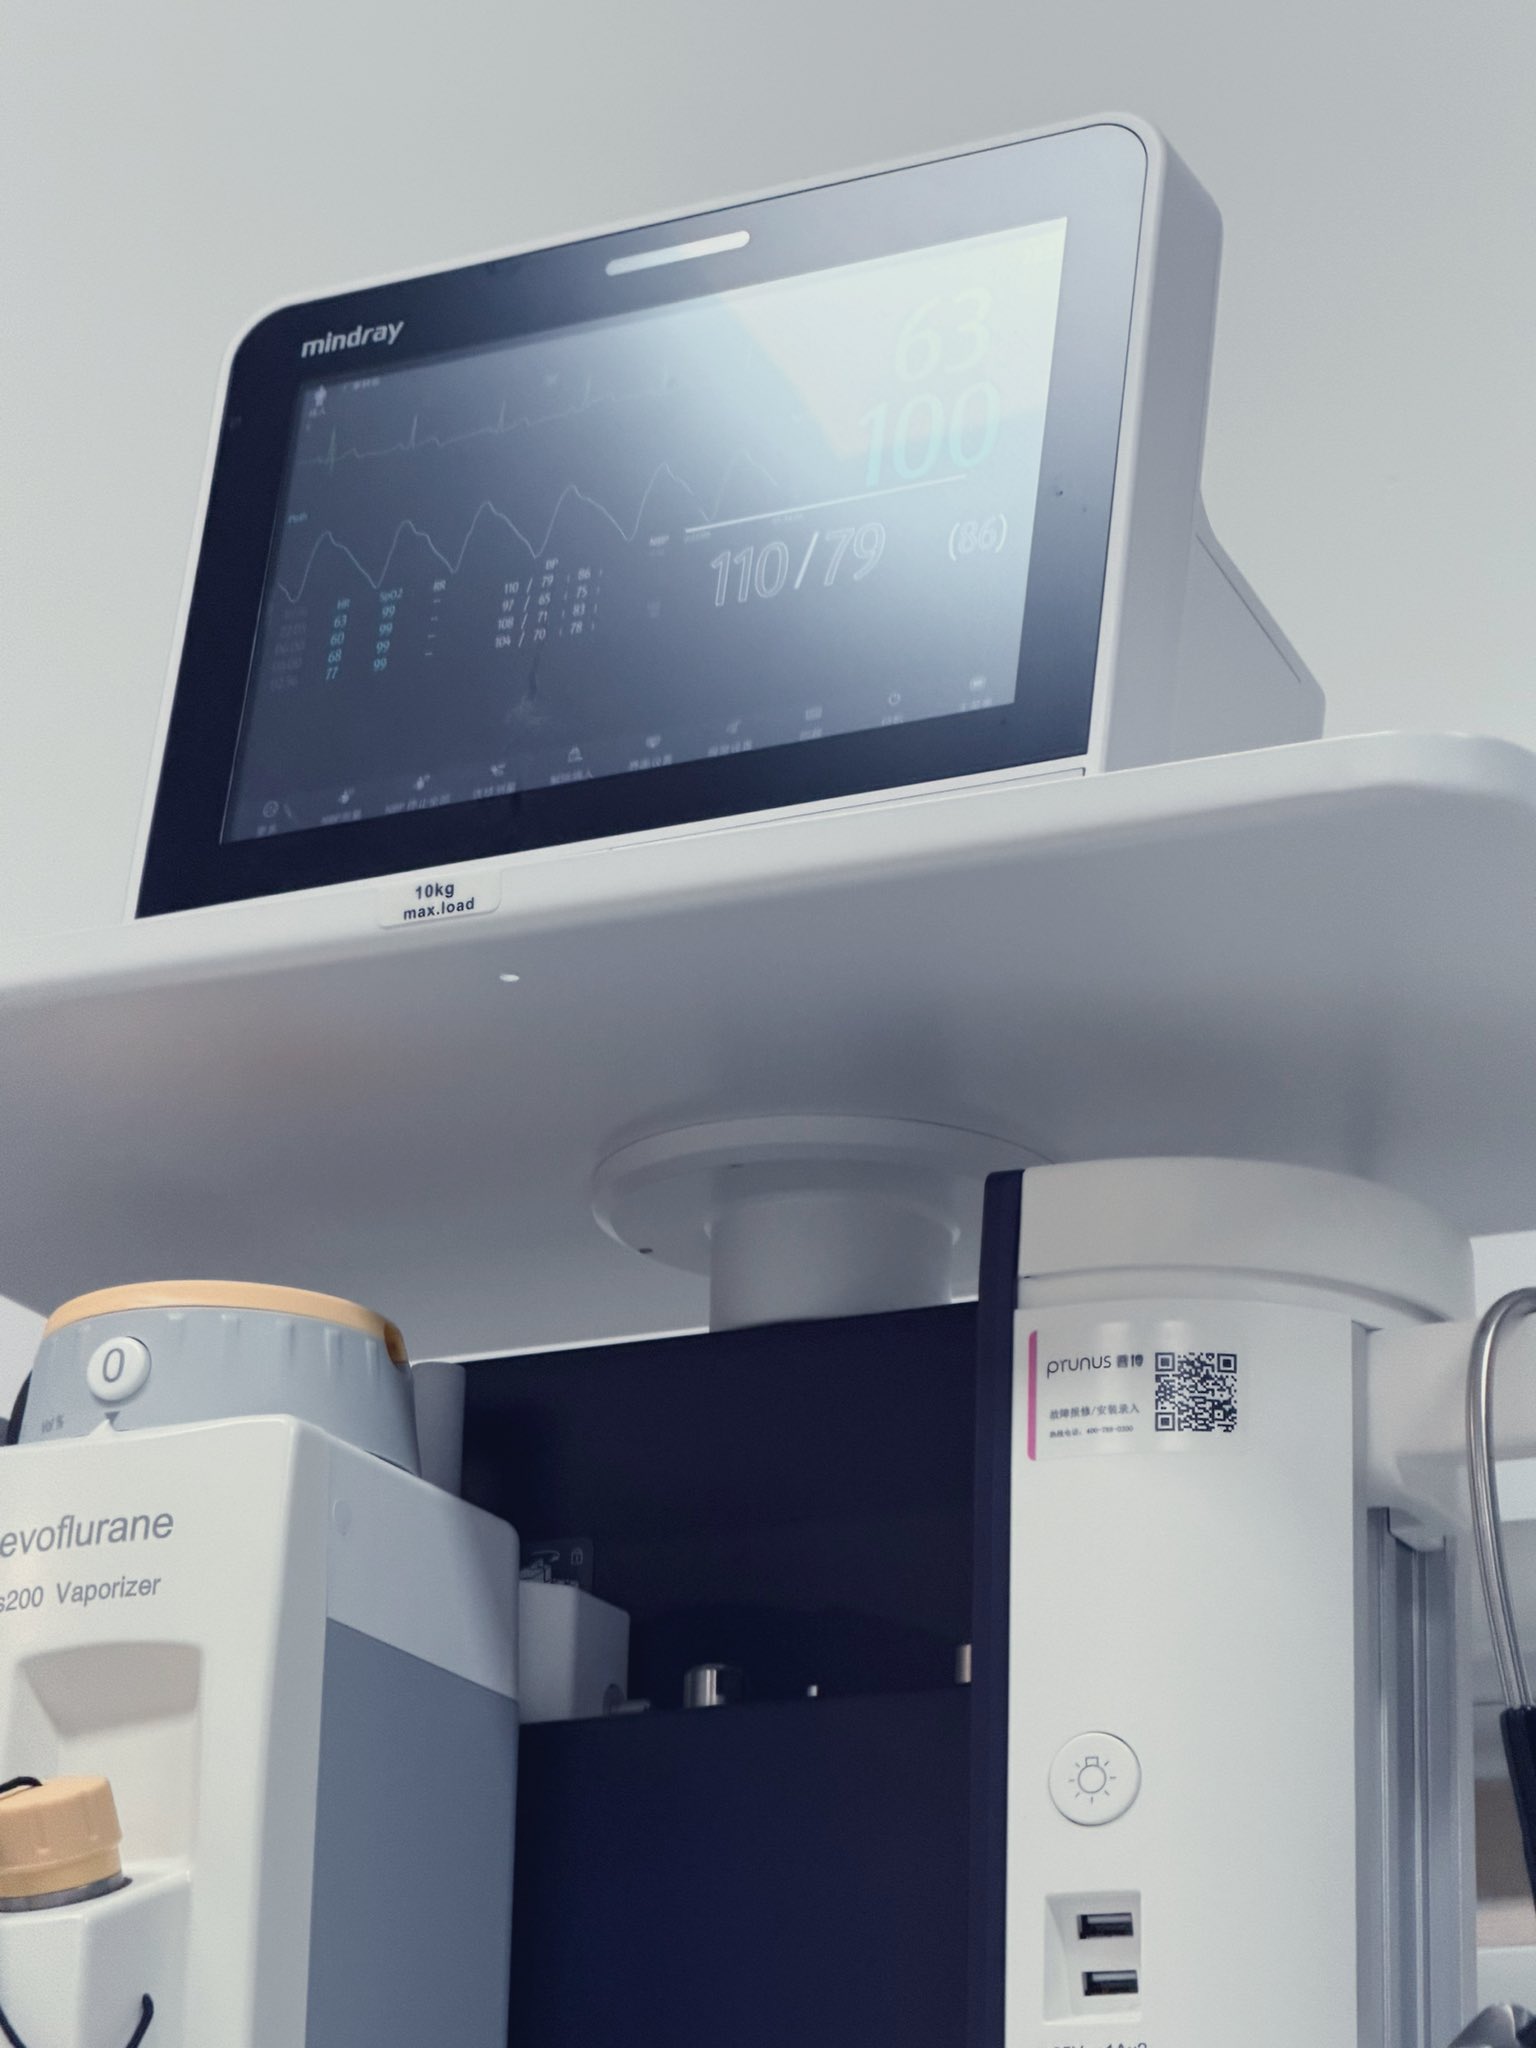

而临床处理药物中毒中,其实医生更常用的做法是保守、支持性的治疗,比如补液,促进代谢,必要时镇静,以及监测生命体征防治并发症。

而临床处理药物中毒中,其实医生更常用的做法是保守、支持性的治疗,比如补液,促进代谢,必要时镇静,以及检测生命体征防治并发症。